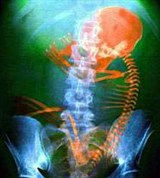

Эмбриоло́гия (от эмбрион и логос — слово, учение), наука о предзародышевом развитии (образование половых клеток), оплодотворении, зародышевом и личиночном развитии организма. Выделяют эмбриологию животных и человека и эмбриологию растений. Различают общую, сравнительную, экспериментальную и экологическую эмбриологию. Основоположники эмбриологии — Гиппократ и Аристотель, а в новое время — К. Ф. Вольф и К. М. Бэр; А. О. Ковалевский и И. И. Мечников заложили основы эволюционной эмбриологии.

В своем первоначальном значении эмбриология обозначала науку о развитии зародышей до их выхода из оболочек, то есть до их вылупления или рождения. В настоящее время предмет эмбриологии трактуется более широко, включая в себя весь онтогенез — процесс индивидуального развития, по крайней мере, начиная с момента оплодотворения (и даже с более ранних процессов формирования половых клеток) и до конца жизненного цикла. Современное учение об онтогенезе часто называют также биологией развития. Фактически биология развития и эмбриология — синонимы.